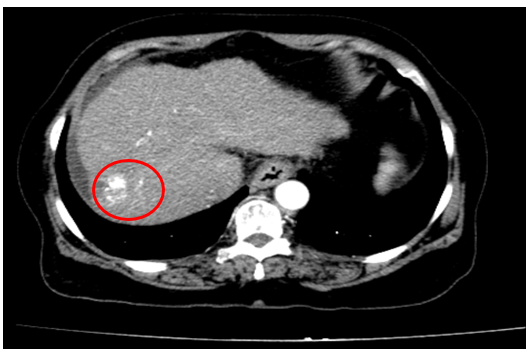

Tháng 01/2025 Bệnh nhân ở nhà xuất hiện mỏi, vàng da, ngứa kèm sốt kéo dài một tháng, đợt này đau bụng mạn sườn phải, kèm vàng da tăng dần, đi khám ở bệnh viện tuyến dưới, siêu âm có sỏi đường mật gan trái kích thước 22×41 mm. Bệnh nhân được chuyển đến bệnh viện Bạch Mai và được chụp CT ổ bụng phát hiện, kết quả: Gan có kích thước bình thường, bờ đều, nhu mô hạ phân thuỳ IV có ổ tổn thương dạng dịch kích thước 40x53mm, trong có sỏi lớn đường kính 35mm.

Hình 1. Hình ảnh sỏi đường mật tạo ổ áp xe gan – đường mật gan trái( vòng tròn màu đỏ). Giãn nhẹ đường mật trong gan hai bên. Dày thành nhẹ ngã ba đường mật trên phim chụp cắt lớp vi tính.